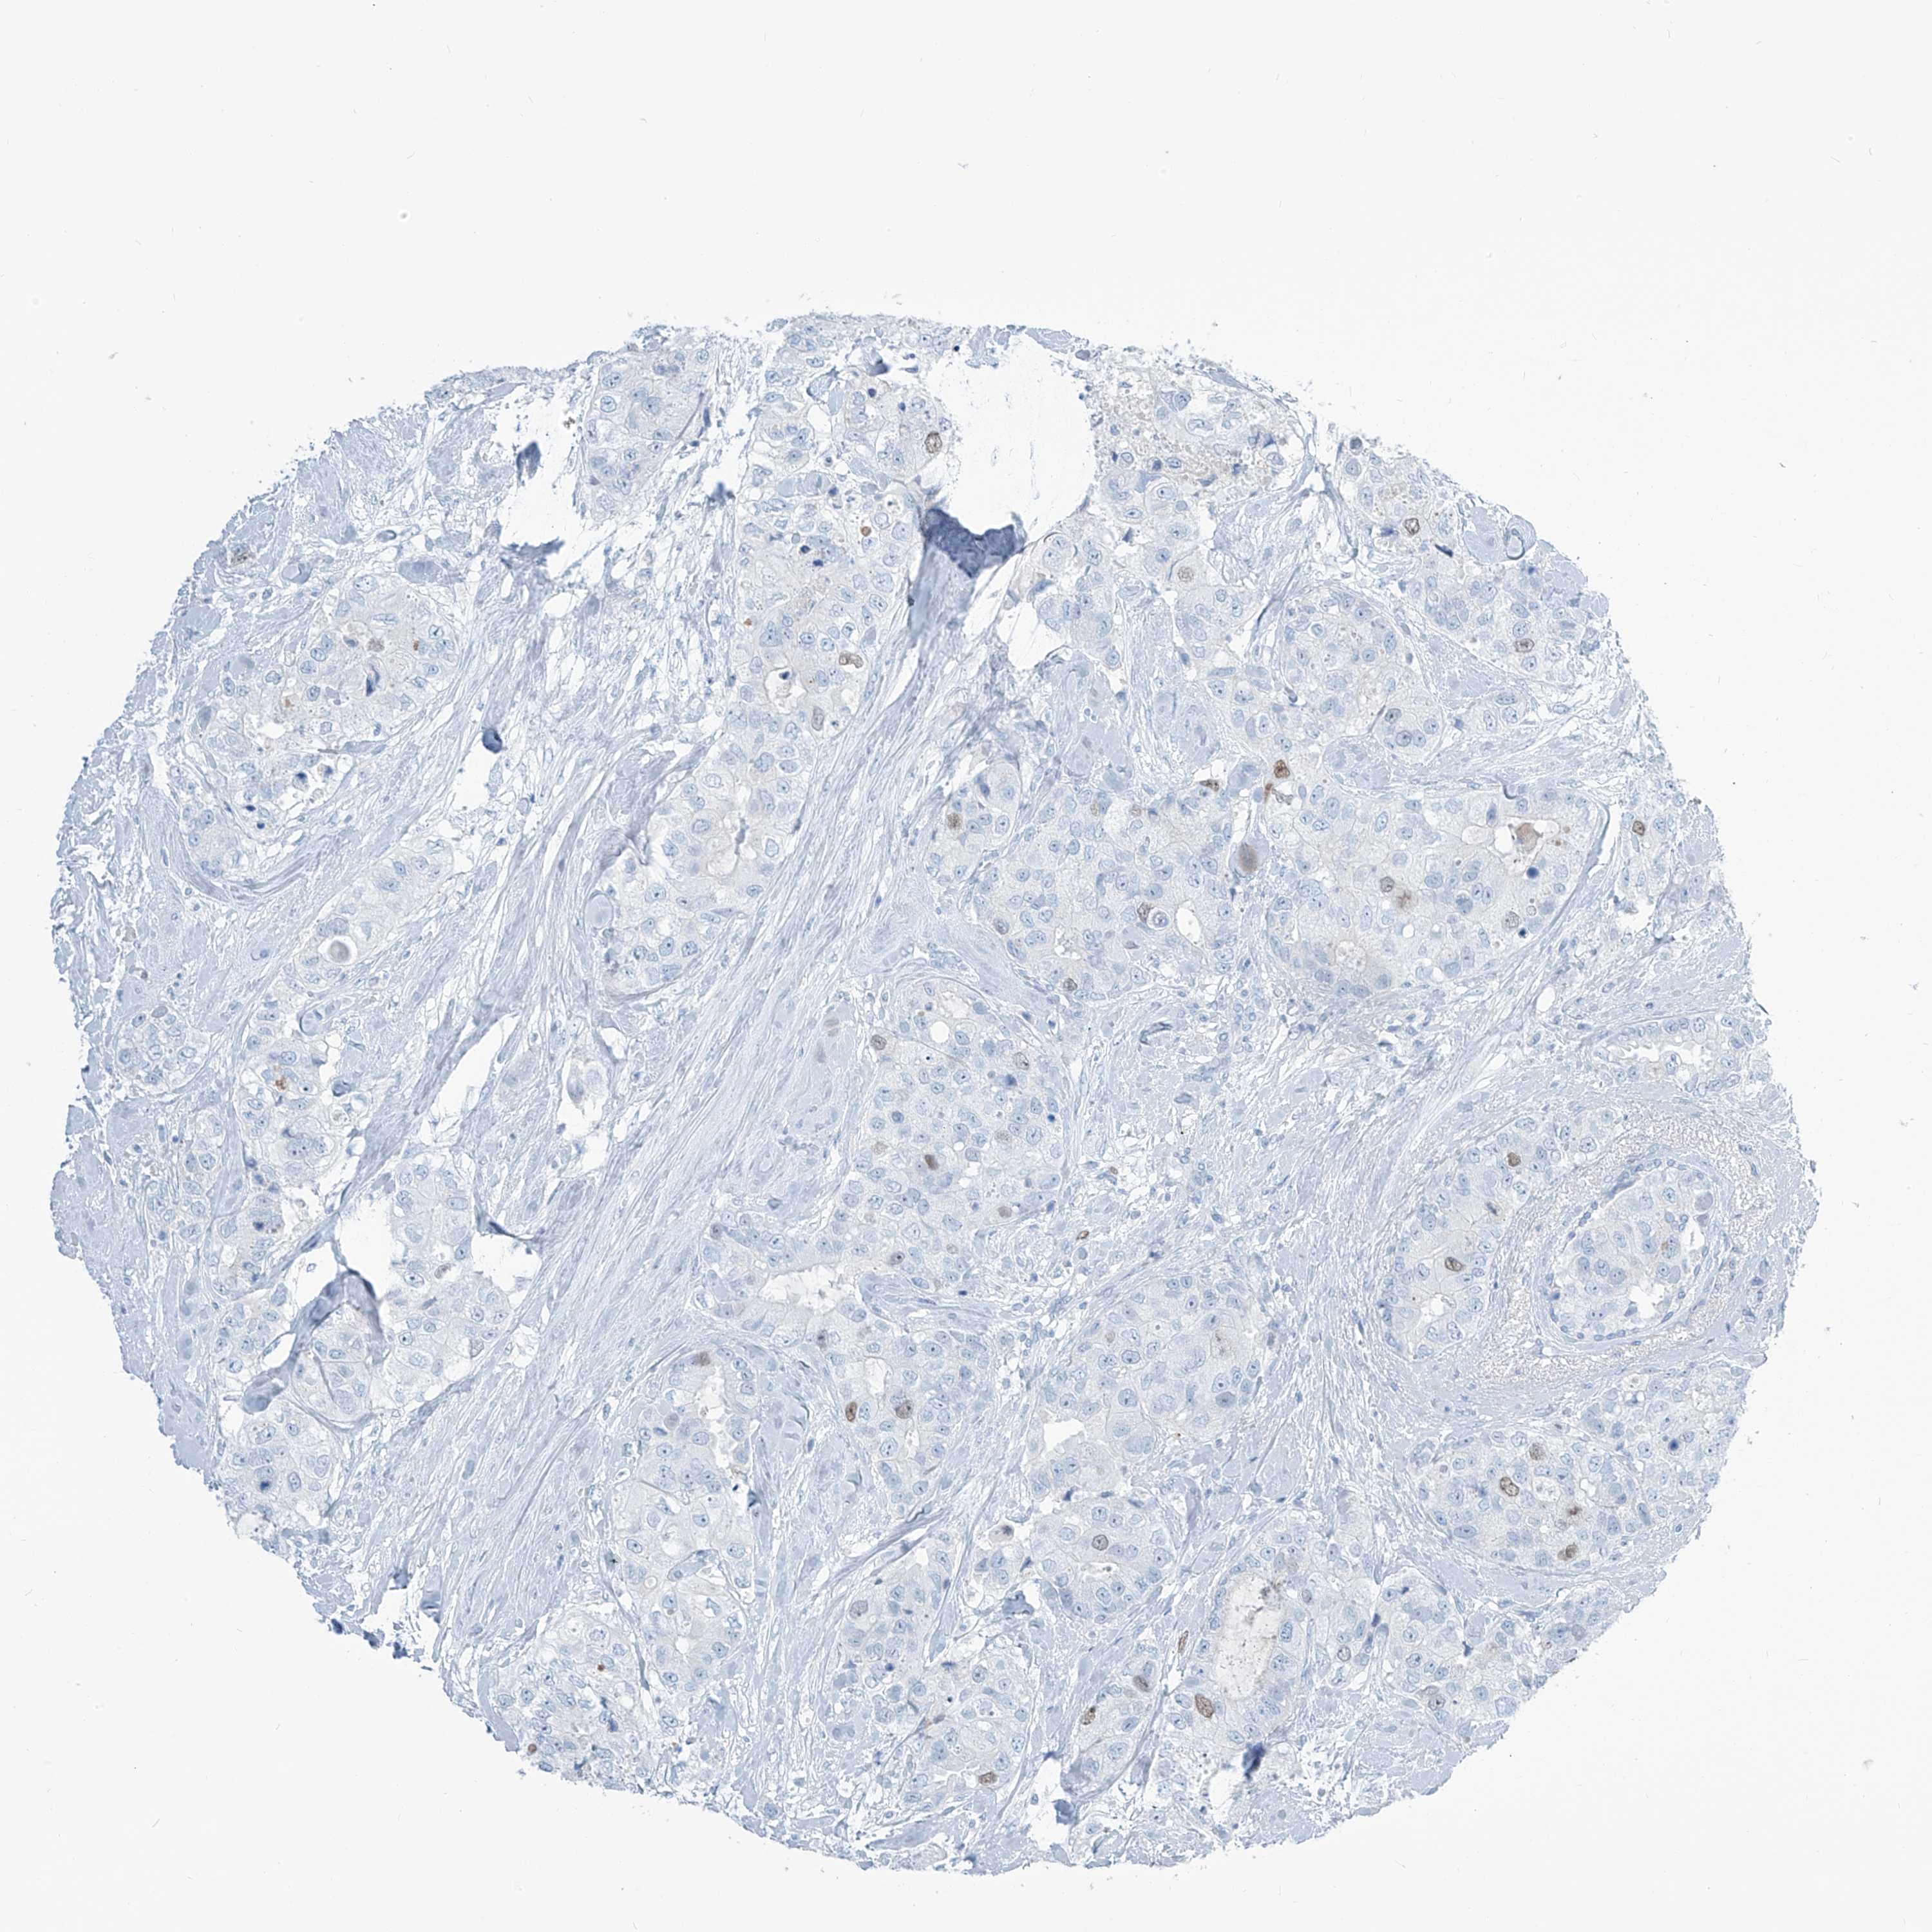

BRCA TCGA BRCA VALIDATION PROTEIN EXPRESSION

ANTIBODIES

AND

VALIDATION